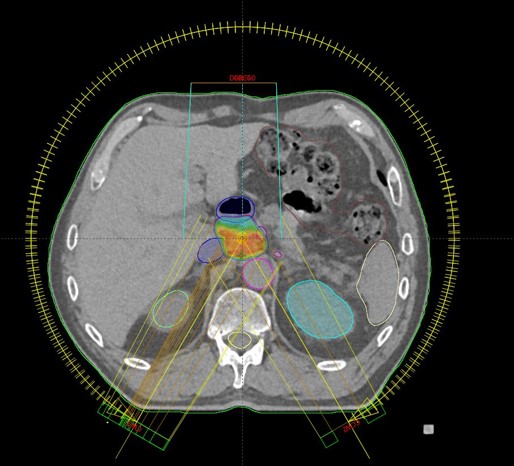

SBRT ppt recidivum locoregionalis tm oesophagei (30.09.2020. - 07.10.2020., TD 35 Gy/5 fr.)

SBRT lymphonodi intraabdominalis (22.11. - 26.11.2021.)

SABR meta hepatis (16.03.-24.03.2023.)